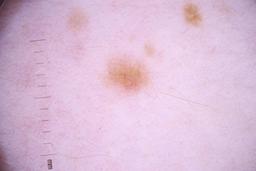

ISIC_4077341

Clinical

| Field | Value |

|---|---|

| acquisition_day | 1 |

| age_approx | 50 |

| anatom_site_1 | Trunk |

| anatom_site_2 | Anterior trunk |

| concomitant_biopsy | False |

| dermoscopic_type | contact non-polarized |

| diagnosis_1 | Benign |

| diagnosis_confirm_type | serial imaging showing no change |

| family_hx_mm | False |

| image_type | dermoscopic |

| lesion_id | IL_9238622 |

| patient_id | IP_1969685 |

| personal_hx_mm | True |

| sex | male |

Columns

Showing first 50 images.